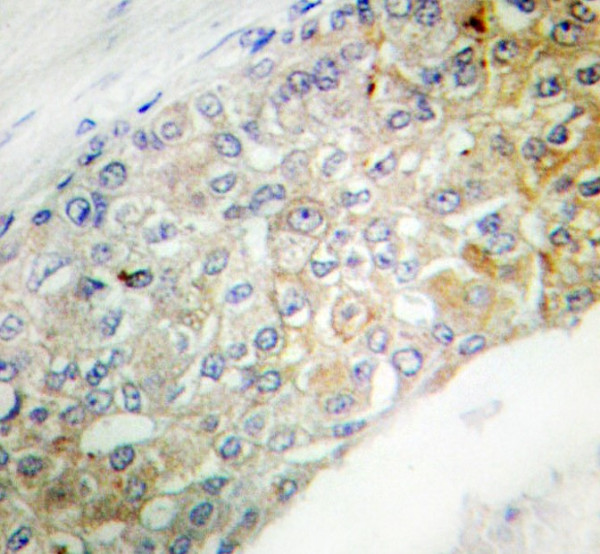

Product information "Anti-Insulin Receptor"

| Application: | ICC, IF, IHC (paraffin), WB |

| Immunogen: | Synthetic peptide of Human CXCR7 / CD187 (a.a. 1326-1375) |